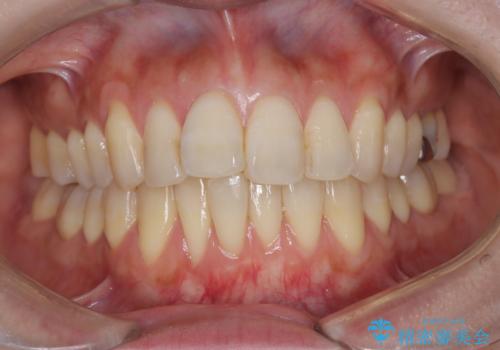

半年で改善した上顎前歯の突出

- 患者様は、上顎前歯の突出を改善したいとのご希望で来院されました。診断の結果、噛み合わせや全体的な歯列には大きな問題がないため、上顎のみを対象とした部分矯正が最適と判断しました。特に患者様は短期間での治療完了を希望されていたため、治療期間を約半年と設定しました。審美ワイヤーを用い、前歯を後方に移動させることで、自然で整った仕上がりを目指しました。治療計画は、患者様のスケジュールや希望を最大限考慮し、実現可能な目標を設定しました。

部分矯正では、治療範囲が限定されるため、力のコントロールが非常に重要です。本症例では、前歯を後方に移動させる際、周囲の歯や噛み合わせに影響を及ぼさないように細心の注意を払いました。また、短期間の治療でも歯の移動に伴う歯肉や歯根への負担を抑えるため、定期的なチェックと調整を行いました。患者様には矯正装置の清掃を徹底していただき、虫歯や歯周病のリスクを回避しました。結果として、予定通りの期間で治療を完了し、患者様には満足していただけました。